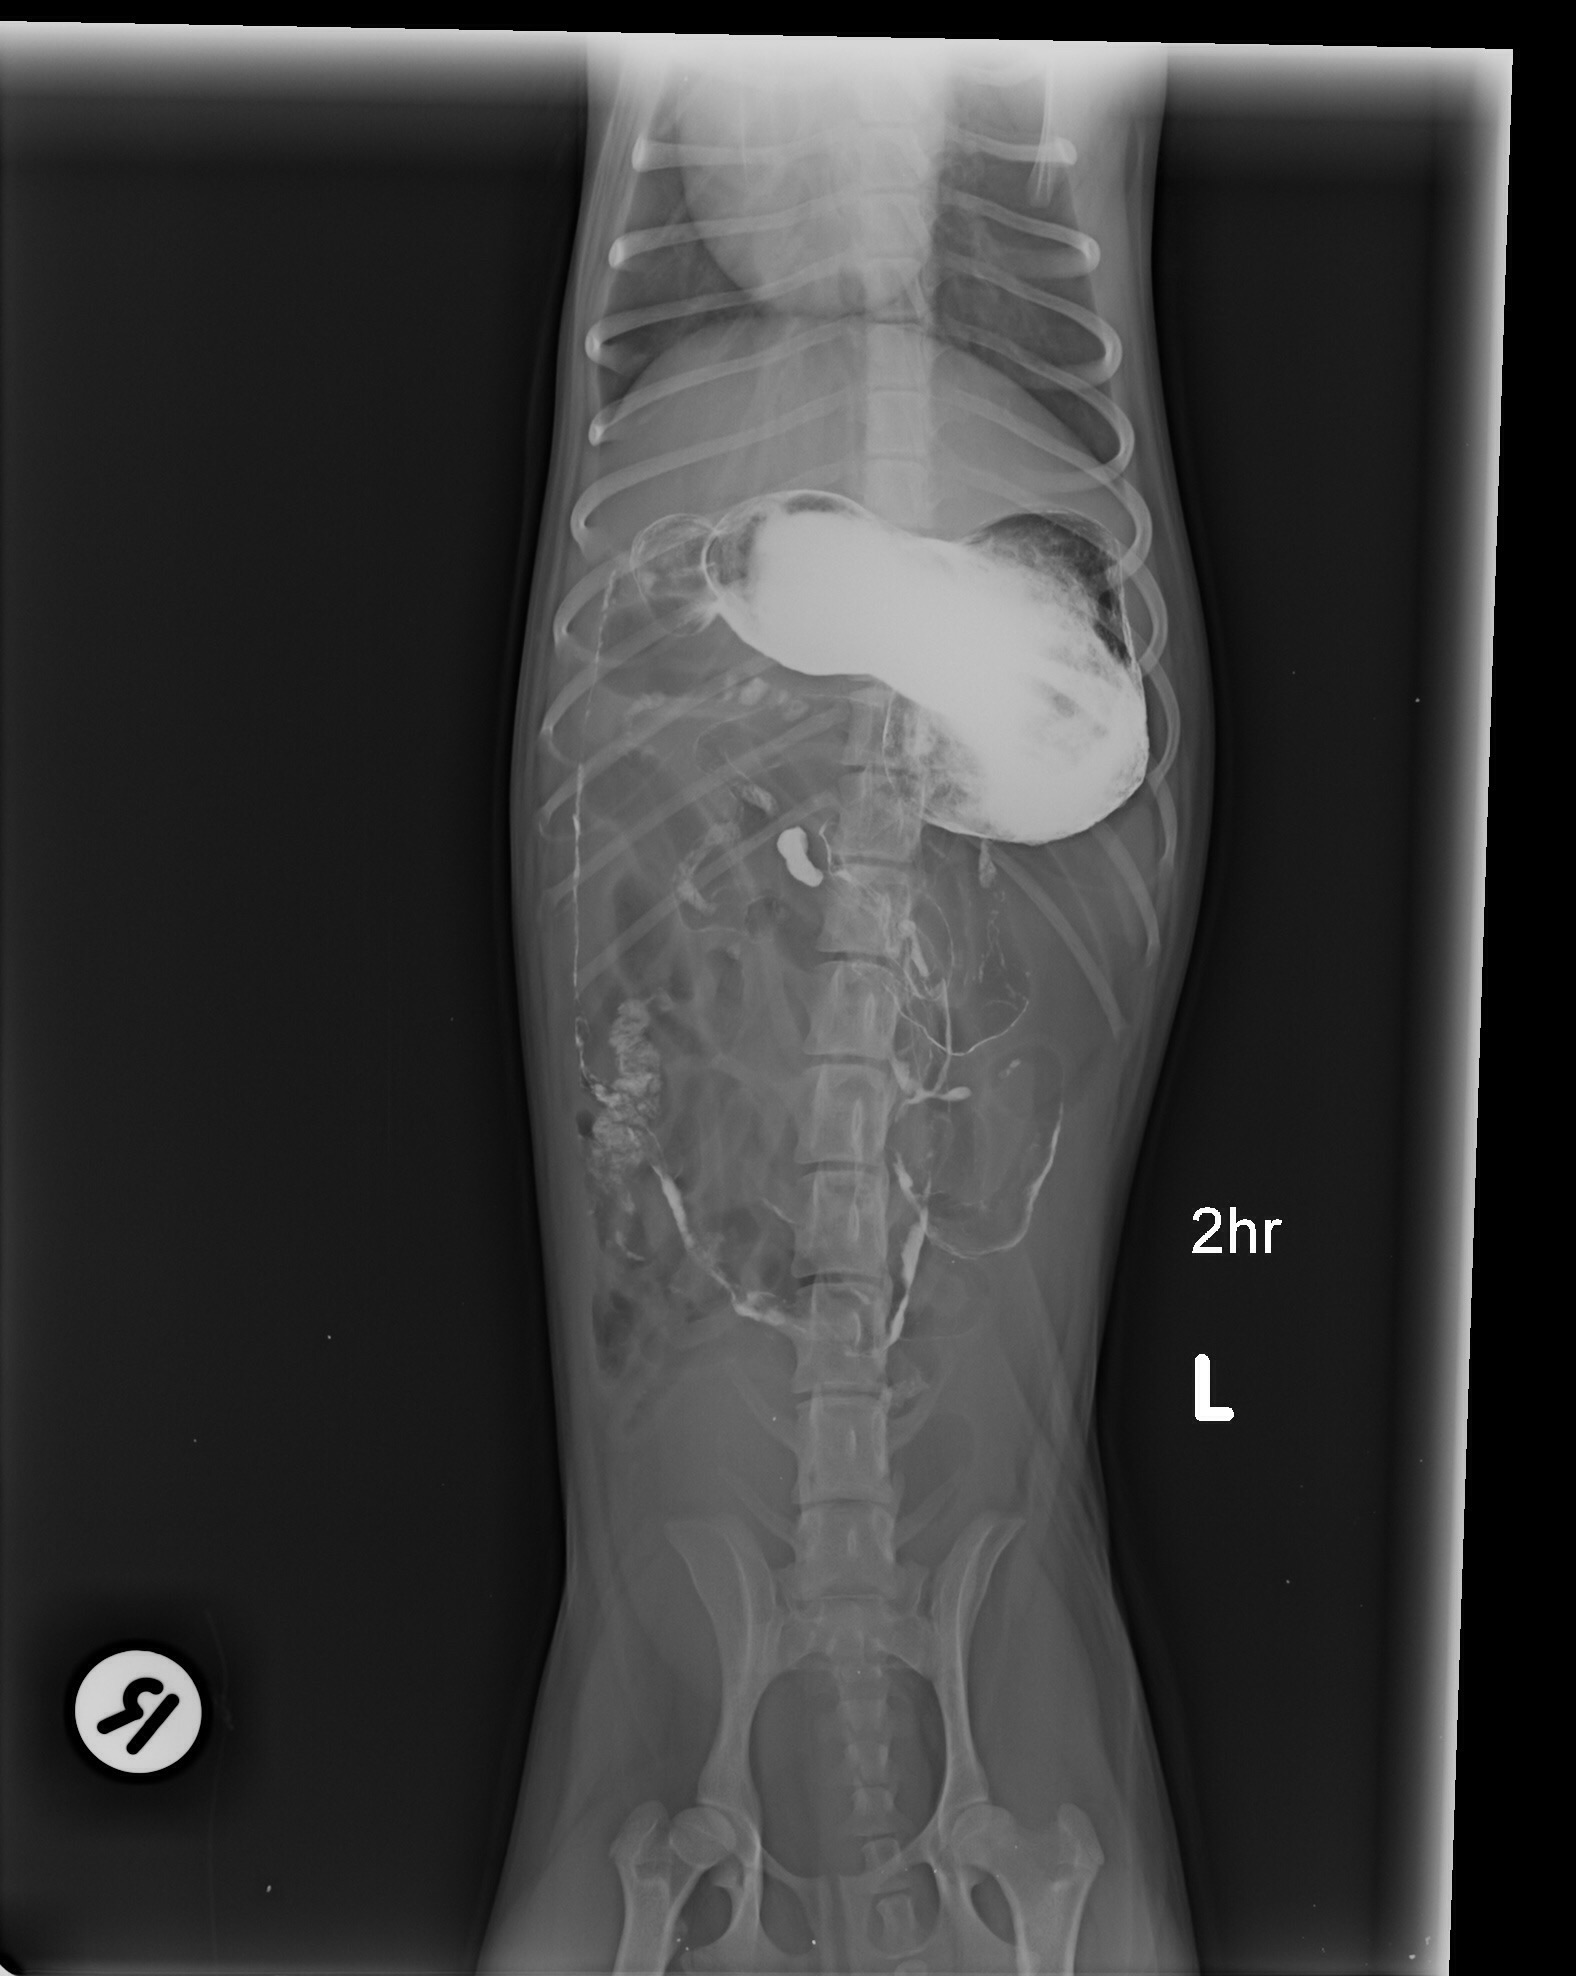

ديروز من بردمش دكتر و اونا نظرشون اين بود كه ممكنه چيزي قورت داده باشه و توي شكمش گير كرده باشه. سوفي xray شد و گفتند مقدار زيادي گاز توي شكمش هست، بهش berim contrast دادن و يكساعت بعد دوباره xray گرفتن و فقط مقدار كمي از كانترست خارج شده بود كه ميگفتن طبيعي نيست بايد خارج ميشده، صبح باز هم xray شد و بيشتر كانترست خارج شده بود ولي ميگفتن چون هنوز كمي اش مونده ممكنه چيزي باشه و بايد عمل بشه، اما من هنوز متقاعد نشدم، آيا واقعا اگه چيزي بود نبايد توي سه بار عكس گرفتن اونم بعد كانترست نباد نشون بده؟ سوفي بينهايت آب بدنش كم شده و واقعا نياز به سرم داره، ديگه بالا نياورده اما تا ديشب اسهال داشت. اونا بيست و چهار ساعت براي عكس نگهش داشتن تازه امروز گفتن بايد بيست و چهار ساعت ديگه بمونه براي سرم، اينجوري من فقط شارژ ميشم بدون اينكه مطمئن باشم قضيه چيه و اين كوچولوي زبون بسته هم هنوز حالش خوب نيست، من جواب ها رو براتون ايميل ميكنم، اگه نظرتون رو بگيد واقعا مديونتون ميشم.